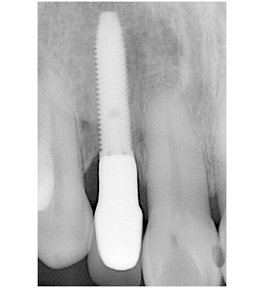

右上の歯の前から2番目を抜歯し、即時にインプラントを施した前歯部・審美領域の治療

- 被せ物が脱離した右上2は歯根破折をしており、保存不可能と判断されたため抜歯と同時のインプラント埋入を計画。抜歯と同時にインプラント埋入。そのインプラントの生着を待って上部構造の装着を行なった

- 435,000円(税別)

- 3ヶ月